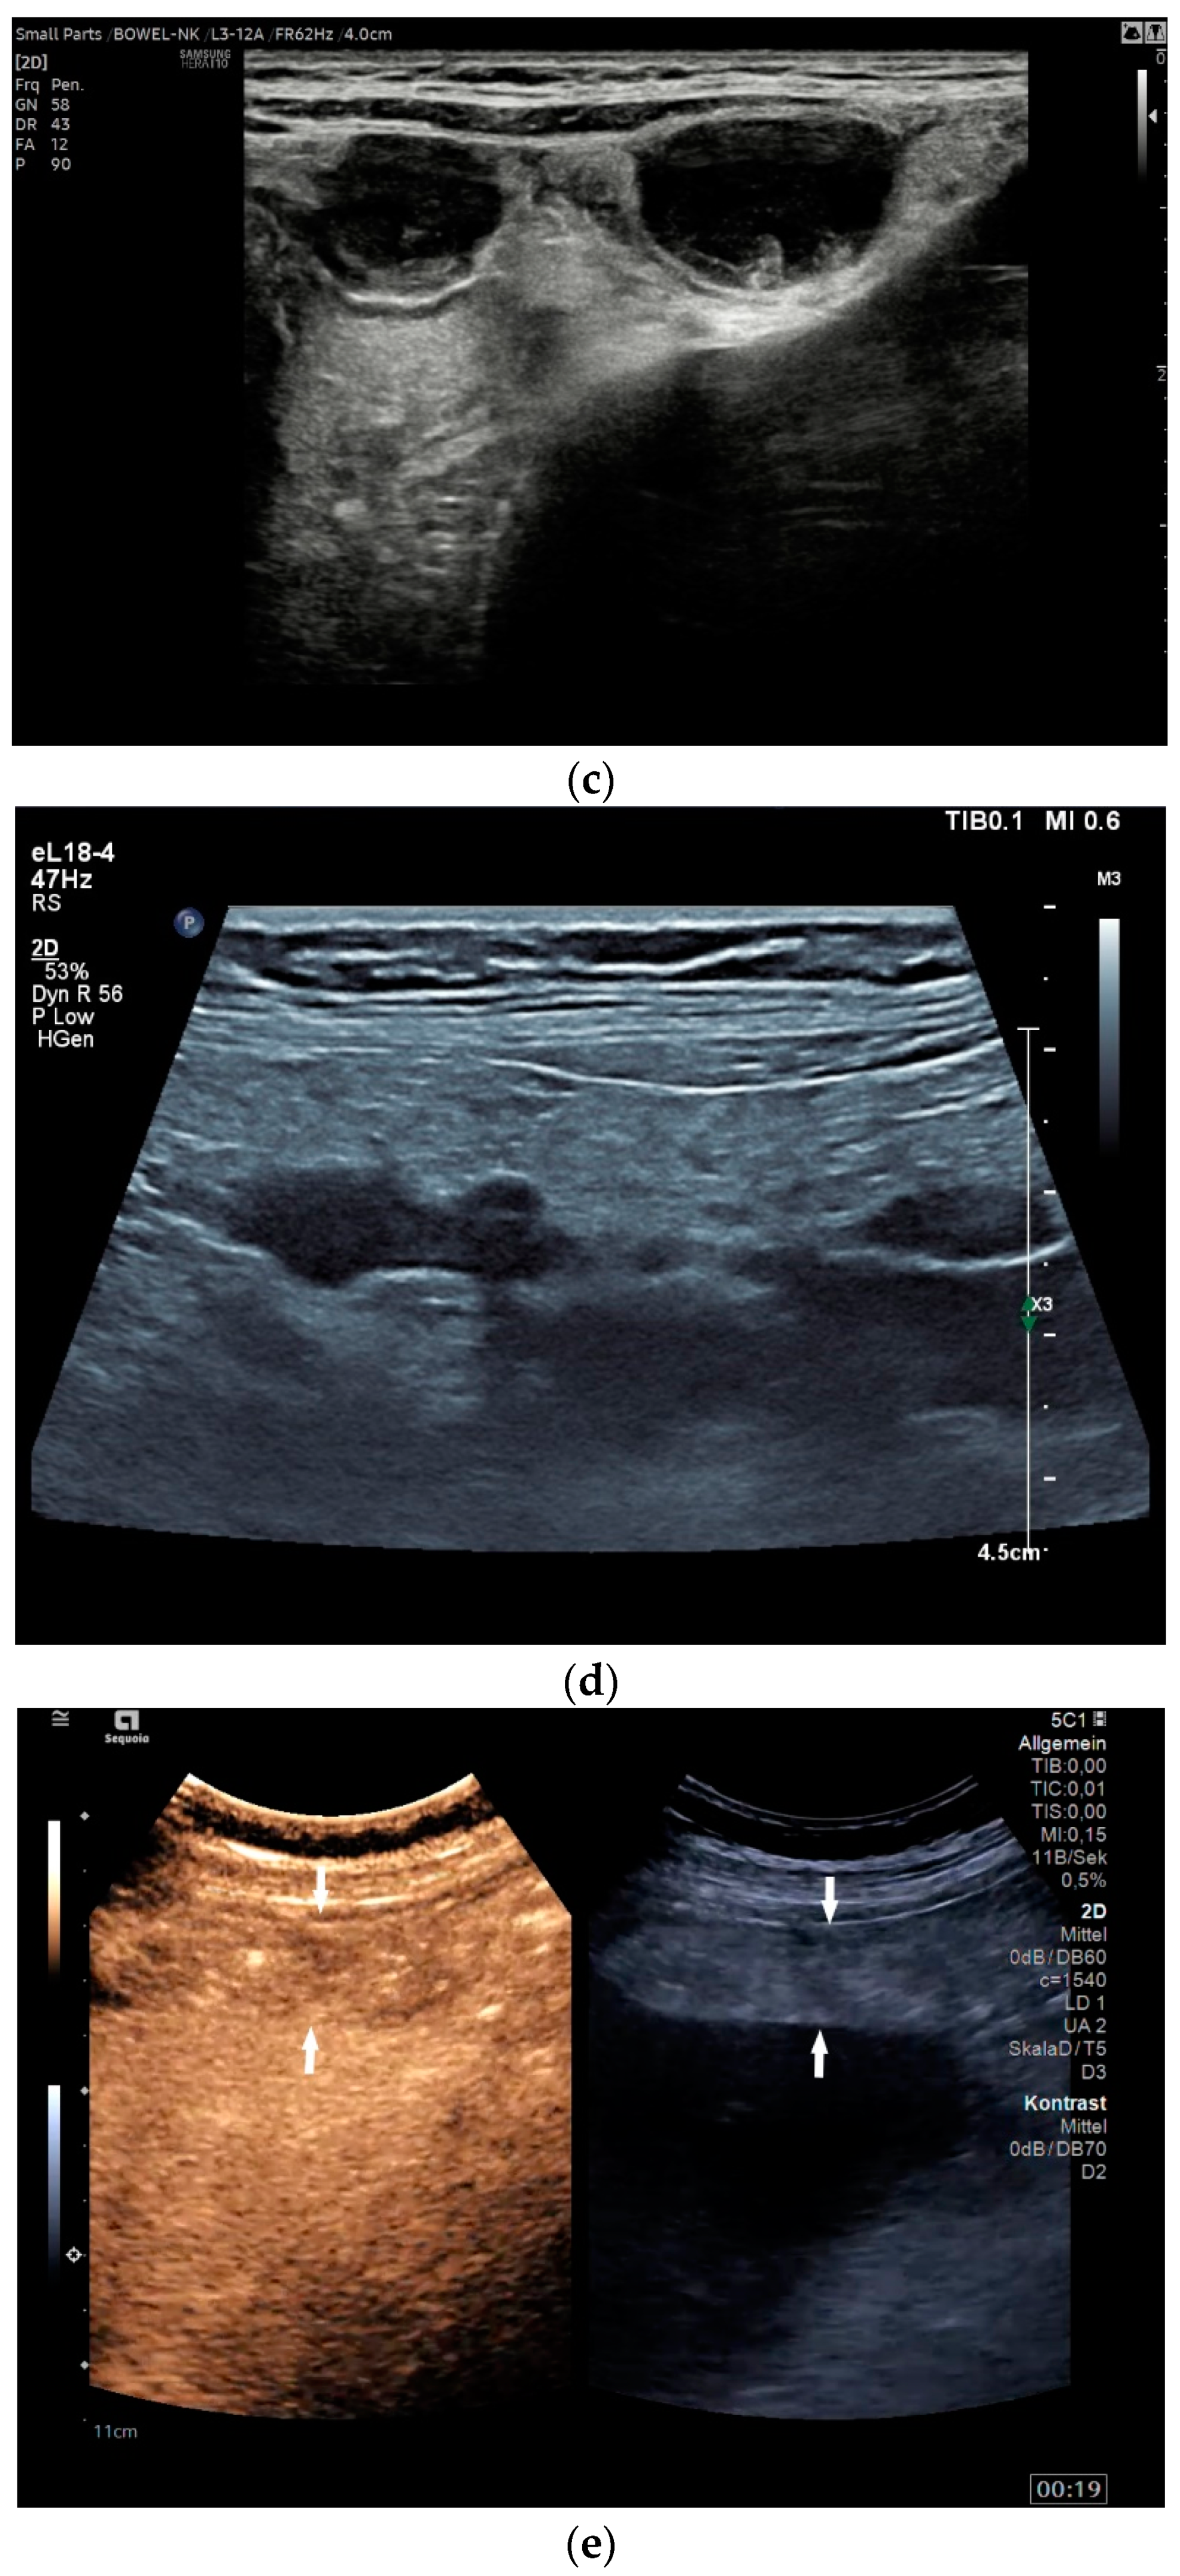

What can be seen sonographically? Ascites can be either diffuse or focal type [Figure 1a,b]. Due to the protein and cell content, these tend to be echogenic, rather than non-echoic. Attention must be paid to enlarged lymph nodes at the same time. Any thickening of the peritoneum and mesentery must be specifically searched for. This also applies to macronodular changes in the peritoneum and mesentery [Figure 1c–h]. The smallest speck-like deposits are usually not visible on ultrasound [36]. With ascites, it may be possible to observe the adhesions [31,37]. Kumar et al. were able to histologically detect granulomatous inflammation in 17/19 (89%) patients using ultrasound-guided needle biopsy of omental thickenings. In a country like India, the authors interpreted this as a manifestation of tuberculosis [32].

Figure 1.

Typical changes in the peritoneum, mesentery, and omentum in patients with tuberculosis. Ascites with pronounced septa (a). Ascites encapsulated between the abdominal wall and colon (b). Omental thickening with non-echoic caseous abscesses and few echogenic contents (c); hypoechoic nodules in hyperechoic thickened peritoneum (d). Significantly thickened hyperechoic peritoneum in B-mode US (right side of image) (marked with arrows). In CEUS, the thickened peritoneum is contrast enhanced in the arterial phase (e). In the parenchymal phase, it shows a decrease in enhancement (f). The thickened hyperechoic peritoneum shows a non-echoic lesion (arrow) (g). In the CEUS, this is not enhanced and instead shows a hyperenhanced rim. This corresponds to caseous necrosis (h).